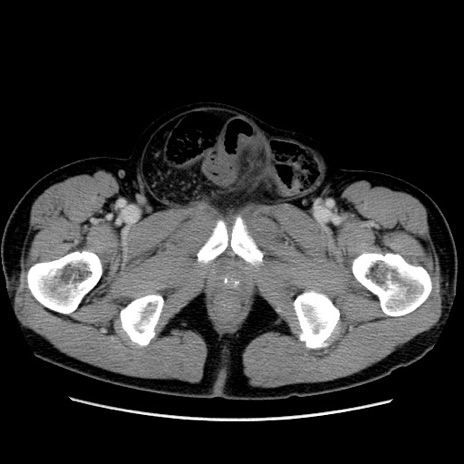

症例34(横断像)

【症例】60歳代 男性

【主訴】右鼠径部膨隆

【現病歴】1年程前より右鼠径部膨隆あり。自己にて還納可能だったため放置していた。3時間前より右鼠径部の脱出を認め、還納困難となり受診。

【既往歴】高血圧

【身体所見】右鼠径部に小児頭大の膨隆あり。弾性硬であり、用手還納は困難。左鼠径部にも膨隆を認める。脱出はなし。

【データ】WBC 15500、CRP 測定なし